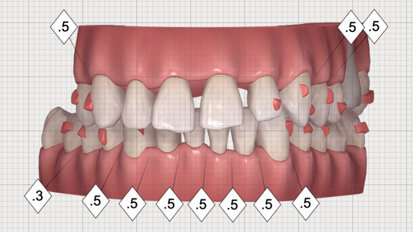

Digitální versus konvenční přístup v estetické stomatologii

Digitální technologie jsou již masivně přítomny v každodenní práci zubních lékařů, a to i v případech kdy je digitální část práce ...